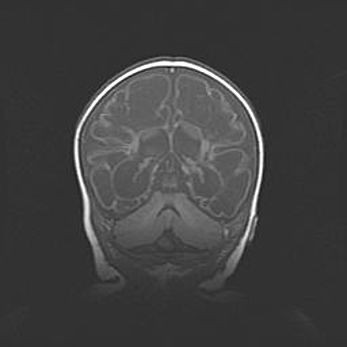

Открытая гидроцефалия.

Возраст: 9 месяцев 12 дней

Вес: 6800 г

Пол: мужской

Окружность головы: 41,5 см

Срок гестации: 28 недель

Гидроцефалия головного мозга у новорожденных имеет характерный признак: опережающий рост окружности головы приводит к визуально хорошо определяемой гидроцефальной форме сильно увеличенного в объёме черепа. Детские неврологи определяют следующие симптомы гидроцефалии у грудничков: выбухающий напряжённый родничок, частое запрокидывание головы, смещение глазных яблок к низу.